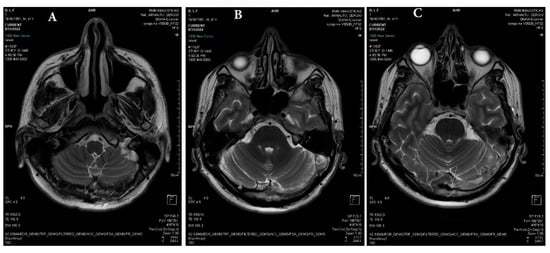

2.2. Neuroimaging Data